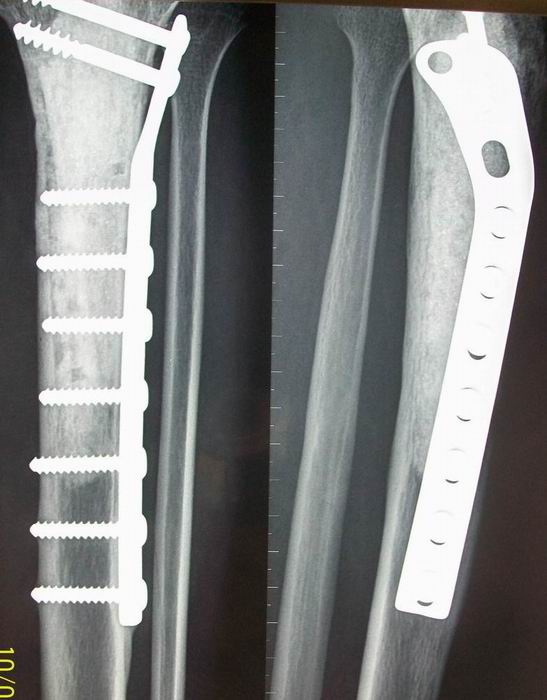

标题: X6452:骨肉瘤术后2年,今健在

病变刮除+植骨+内固定术后改变,结合原片及术后复查片对比。应把膝关节包全。

这就是前几天我发的那个病例,不知道怎么和那个帖子发到一起,所以发到这里了。为了节省空间,所以就把片子裁剪了,去掉了没有意义的关节部分,患者到北京几家医院做的病理,后来到西安做的手术。术后两年了,现在情况还可以。

应该是分化比较高的,看管理员能不能把这个病例和原先发的那个术前的合并在一起啊。

不要掉以轻心,要查肿瘤标记物。可疑复发。